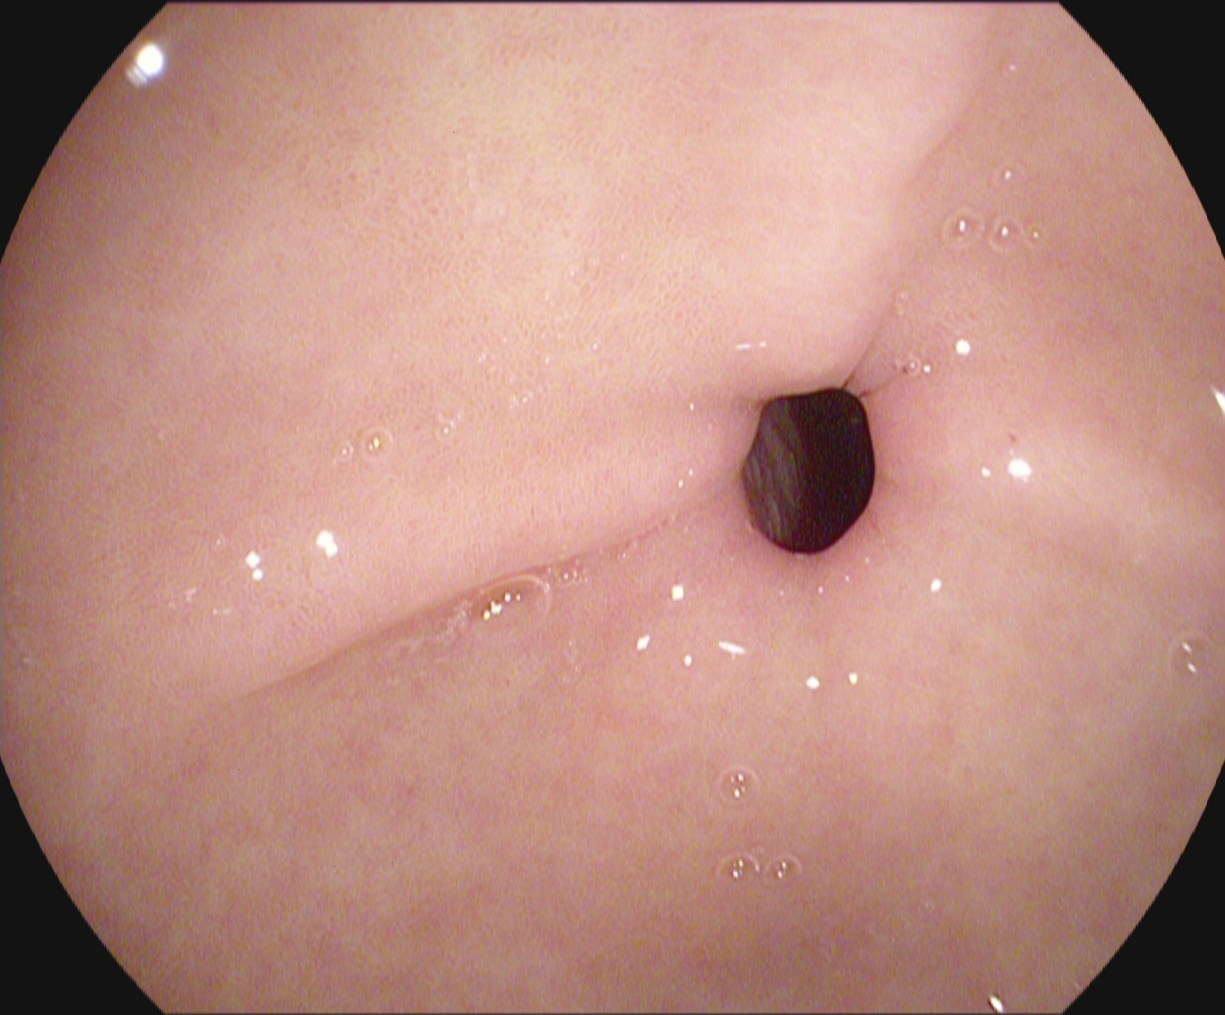

An automatic and efficient Computer-Aided Diagnosis (CAD) system in a clinic could assist medical experts during the endoscopic and colonoscopy procedure to improve the detection rate by finding unrecognized lesions and act as a second observer by providing better insights to the gastroenterologist concerning the presence and types of lesions. With this inspiration, we conducted five experiments to classify 161616 classes of GI tract conditions for the Medico Multimedia Task at MediaEval 2018 (Pogorelov et al., 2018b). One example for each of the 16 classes is depicted in Figure 1.

Figure 1. Sample images of GI findings. Each image represents one of the 16 classes from the dataset used for the Medico 2018 challenge (Pogorelov et al., 2017c, a).